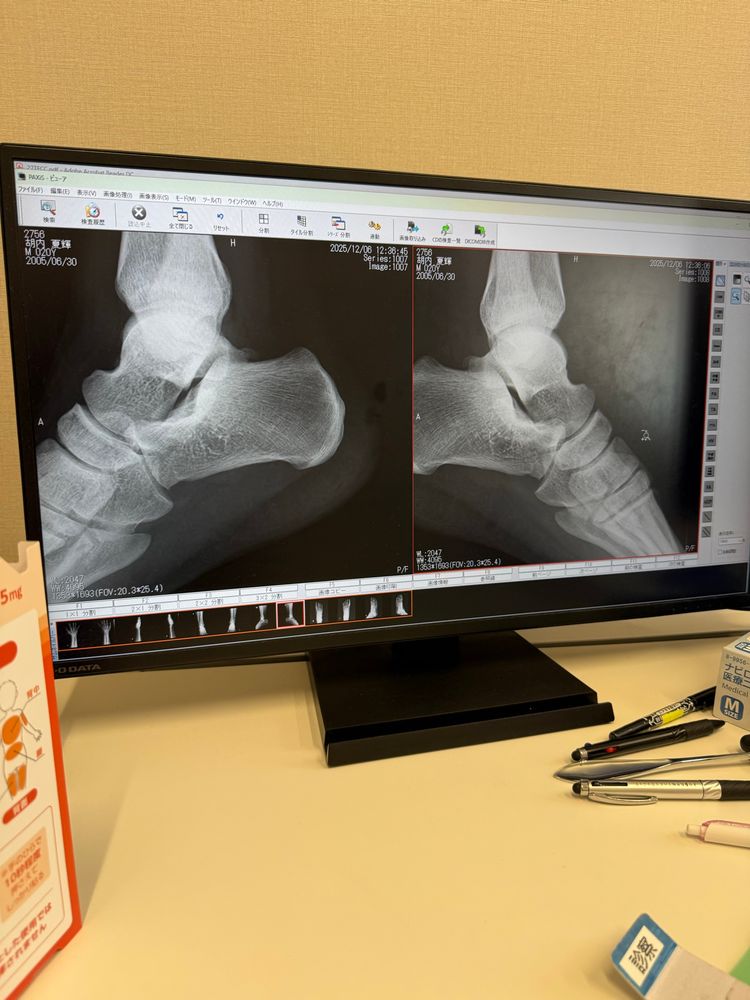

今回撮ったレントゲンたち可愛い

重度の捻挫です😭

靭帯損傷しまちた😭

靭帯損傷したせいでかかとの関節がグラグラする

靭帯損傷うぜー